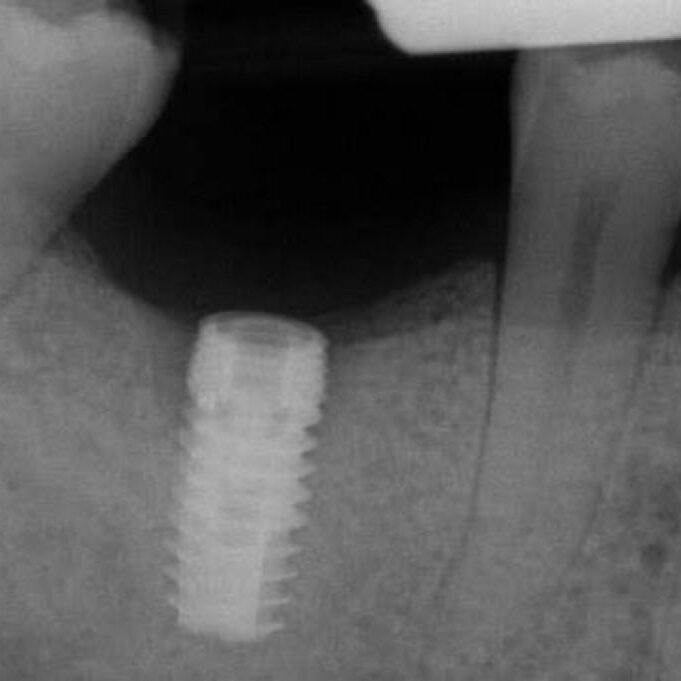

ULTRASONICS: Complications of Abutment Screw Retrieval Secondary to Prior Ultrasonic Attempts

There has been much written on the use of ultrasonics in retrieving fractured screw fragments, which I didn’t think a lot about until May of 2023, as it has not been a part of my fractured screw retrieval algorithm.